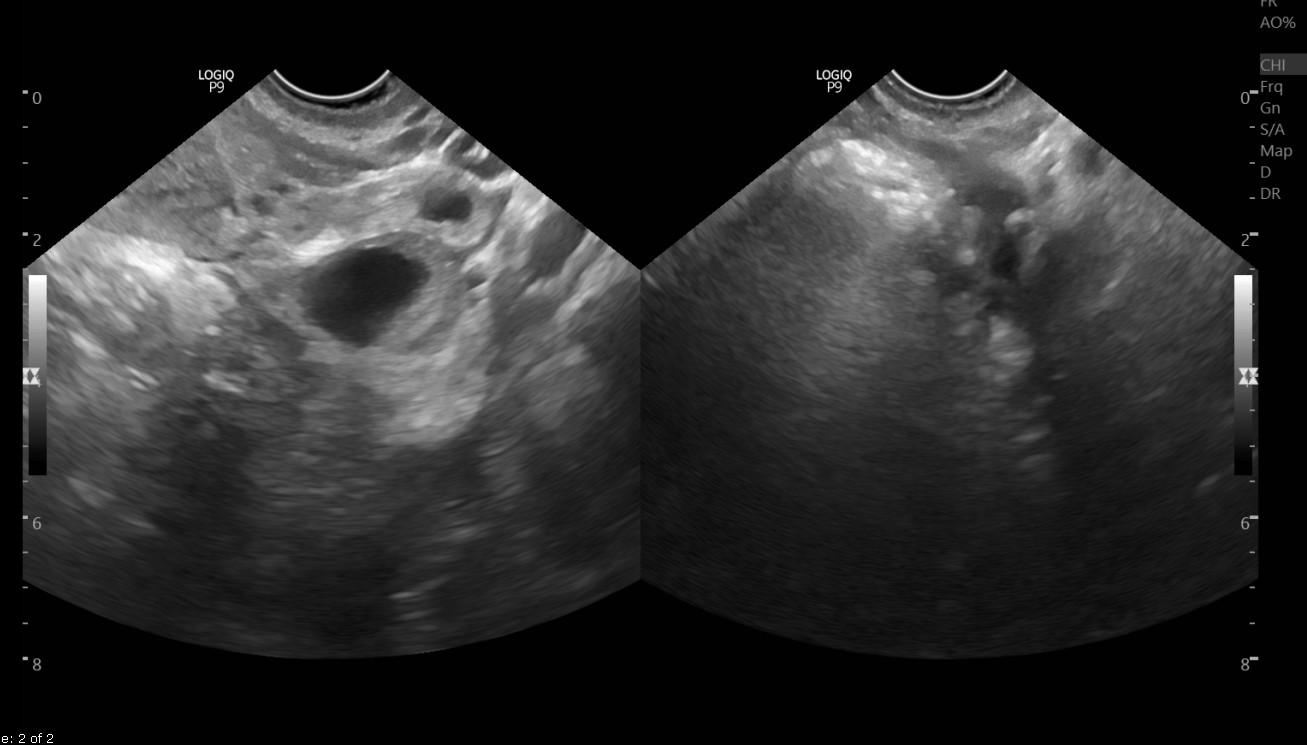

Mang thai là điều vui mừng cho các cặp vợ chồng nhưng bên cạnh đó cũng có nhiều điều lo lắng đi kèm, đặc biệt là với những thai phụ có vết mổ đẻ cũ. Vậy mang thai tại vết mổ đẻ cũ nguy hiểm như thế nào và những lưu ý gì để phát hiện sớm và xử lý kịp thời?

Hiện có nhiều phương pháp điều trị, xử trí khi phát hiện mang thai tại vết mổ đẻ cũ như: Tiến hành nạo hút thai dưới màn hình siêu âm, Điều trị hóa trị kết hợp hút thai, Nạo hút thai kết hợp chèn bóng ống cổ tử cung, Phẫu thuật lấy thai, Cắt tử cung, Kỹ thuật nút mạch khối chửa vết mổ đẻ cũ kết hợp hút thai dưới màn hình siêu âm….